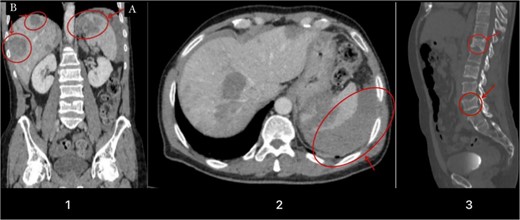

A few weeks later, the patient presented with severe, intermittent colicky pain in the left upper quadrant. MRI and CT scans indicated a ruptured splenic lesion accompanied by a subcapsular hematoma (see Fig. 1). Given the critical nature of his condition, an urgent exploratory laparotomy was performed. The surgery revealed approximately one liter of blood in the abdominal cavity due to venous bleeding from the ruptured splenic lesion. A splenectomy was performed, and multiple large liver lesions suggestive of metastatic disease were noted (see Fig. 1).

Illustrates a contrast-enhanced image obtained during the portal venous phase CT scan. Noteworthy findings include a hypodense lesion in the upper pole of the spleen (Image 1A), multiple liver lesions (Image 1B), evidence of a capsular laceration with adjacent free fluid indicative of intraperitoneal hemorrhage (Image 2), and compression fractures noticed on the vertebral body of T12 and L4 due to metastasis (Image 3).

Postoperatively, the patient was transferred to the intensive care unit in critical condition. His status was complicated by severe back and hip pain that warranted further imaging and laboratory tests. These tests confirmed pathological vertebral fractures at T12 and L4 (see Fig. 1) and elevated liver function tests, supporting the diagnosis of metastatic disease. Despite aggressive surgical intervention and supportive care, the patient’s condition remained critical.